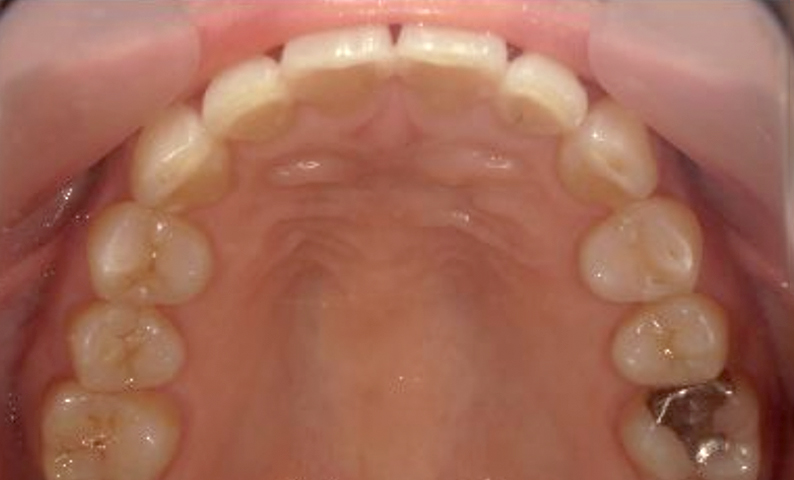

症例_003 下顎だけの部分矯正

治療期間:10ヶ月金額:24万円+税女性前歯のガタガタ下の前歯だけ上顎は補綴治療中

| Before | After |